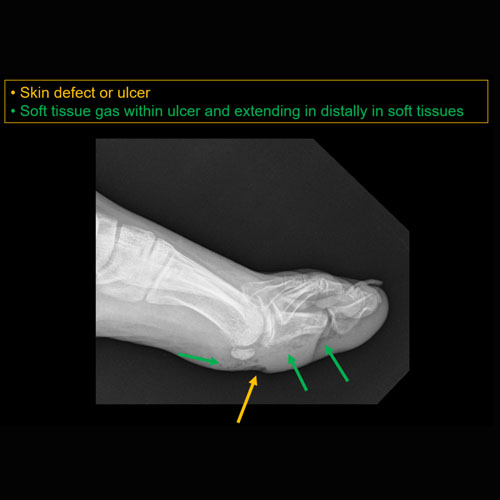

Great toe ulcer.Exam

Skin defect along the plantar/medial aspect of the great toe.

MRI to further evaluate for presence and extent of osteomyelitis.

Urgent (Action Necessary in a few hours)